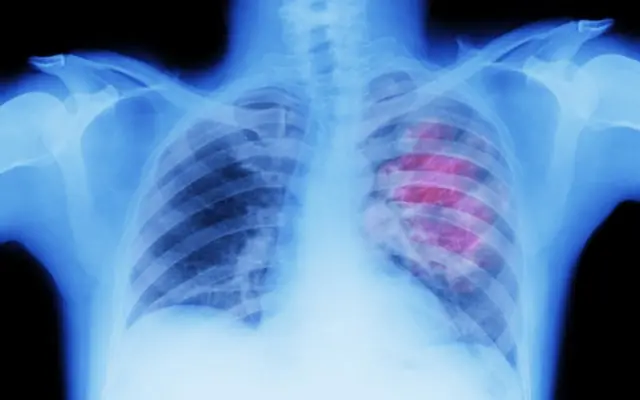

कॅन्सरच्या या 10 लक्षणांकडे कदाचित तुमचं दुर्लक्ष होऊ शकतं

बीबीसीनं कॅन्सरची 10 सामान्य लक्षणं सांगितली आहेत, ज्याकडे अमेरिकन कॅन्सर सोसायटीनुसार तुम्ही दुर्लक्ष करू नये.

सतत खोकला येणं हे फुफ्फुसाच्या कर्करोगाची लक्षण असू शकतं.

तुम्हाला तीन आठवड्यांपेक्षा जास्त काळ त्रास होत असल्यास तुम्ही डॉक्टरांना भेटून त्यांचा सल्ला घ्यावा.